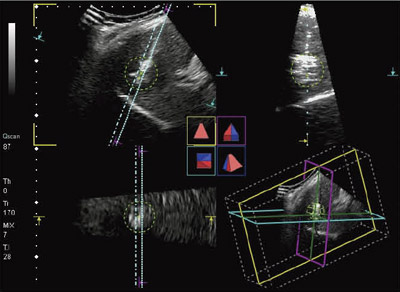

PVT-375MVに穿刺アダプタを装着して穿刺を行う際は,画面上に穿刺アダプタに対応した穿刺ラインが表示される。図7は,4D穿刺モードにおけるファントムのMPR表示である。A面に表示された斜めの2本のラインは,穿刺アダプタの穿刺経路に対応したガイドラインである。平行した2本のラインは,穿刺経路の左右5mmに位置している。MPRのB面は,穿刺経路を交線とする直交面である。A面のガイドラインの範囲内で穿刺針が刺入されたとき,B面中央の破線上を進むことになる。そして,C面は,穿刺経路に直交する。4D穿刺モードのMPR表示では,穿刺経路に対する直交3断面が表示されるので,穿刺針の刺入時に周囲組織との関係の把握が容易である。

さらに,図7に示されるように,任意の半径の球面(ターゲットガイド)を表示することが可能で,腫瘍の広がりやRFAの焼灼範囲の目安として利用することができる。図8に,4D穿刺モードにおけるMulti View表示のファントム像を示す。B面のMulti View像(図8 a)は,穿刺経路に平行な断面の並列表示であり,C面のMulti View像(図8 b)は,穿刺経路の深さごとの断面の並列表示である。腫瘍の広がり,周囲臓器や周囲血管の位置,焼灼範囲の評価が容易である。図9は,RFA治療中の4D穿刺モード像である。ガイドラインに沿ってRFA針が刺入され,焼灼されている。ターゲットガイドの球面を目安に,焼灼状況を三次元的に観察することができる。

図7 4D穿刺モードにおけるファントムのMPR表示